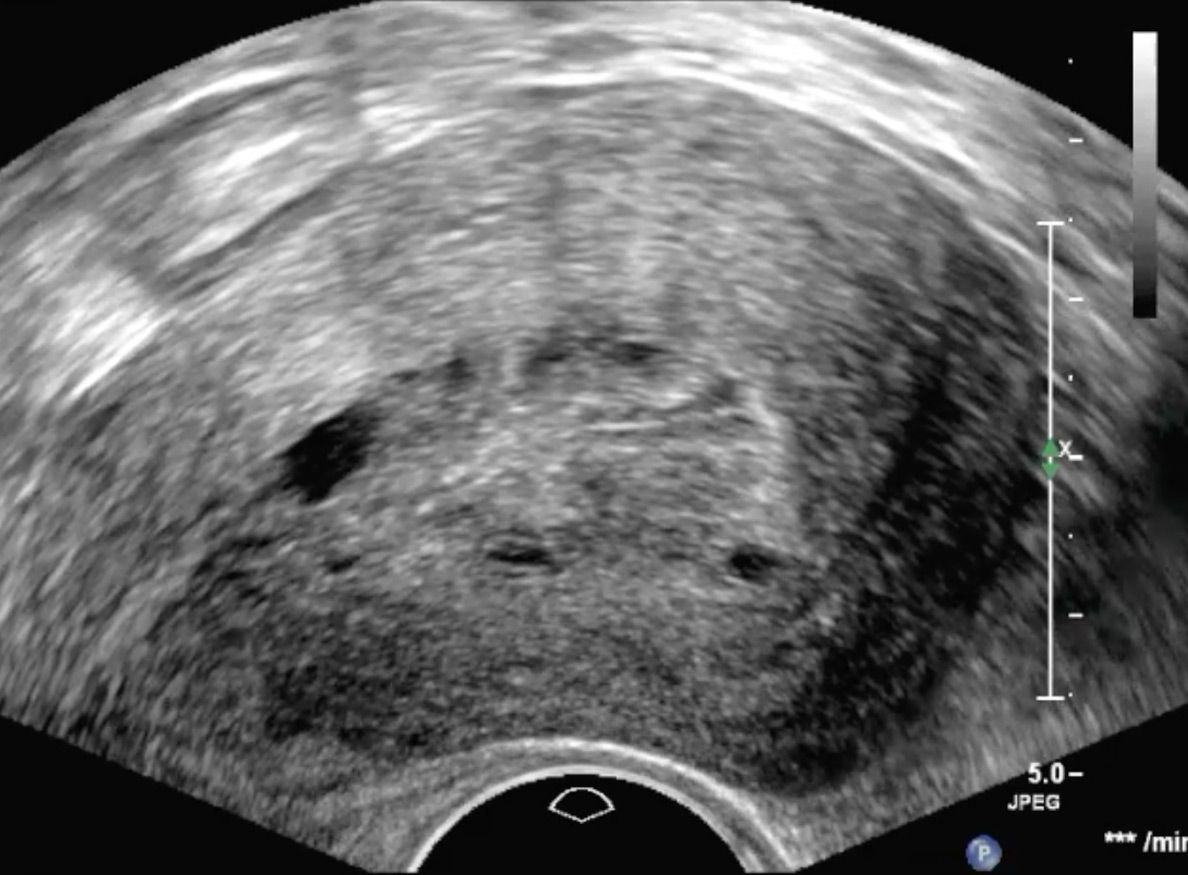

Adenomyosis

Aufgrund der Vielfalt an möglichen Symptomen handelt es sich in der Differentialdiagnostik um ein Chamäleon. Insbesondere die Manifestation innerhalb des Eierstocks (Endometriome, Schokoladenzysten) oder innerhalb der Gebärmuttermuskulatur  weisen ein charakteristisches Ultraschallbild auf. Daher ist die Vaginalsonographie ein wichtiger Bestandteil der Diagnostik zur Erkennung der Endometriose.

Die Endometriose ist eine Erkrankung, die durch Auftreten von Gebärmutterschleimhaut-ähnlichem Gewebe außerhalb der Gebärmutterhöhle  geprägt ist. Das abnorm lokalisierte Gewebe kann ein Vielfalt an Symptomen auslösen. Von zyklusabhängigen Schmerzen, Blutungsunregelmäßigkeiten bis hin zum unerfüllten Kinderwunsch können diese Probleme reichen.